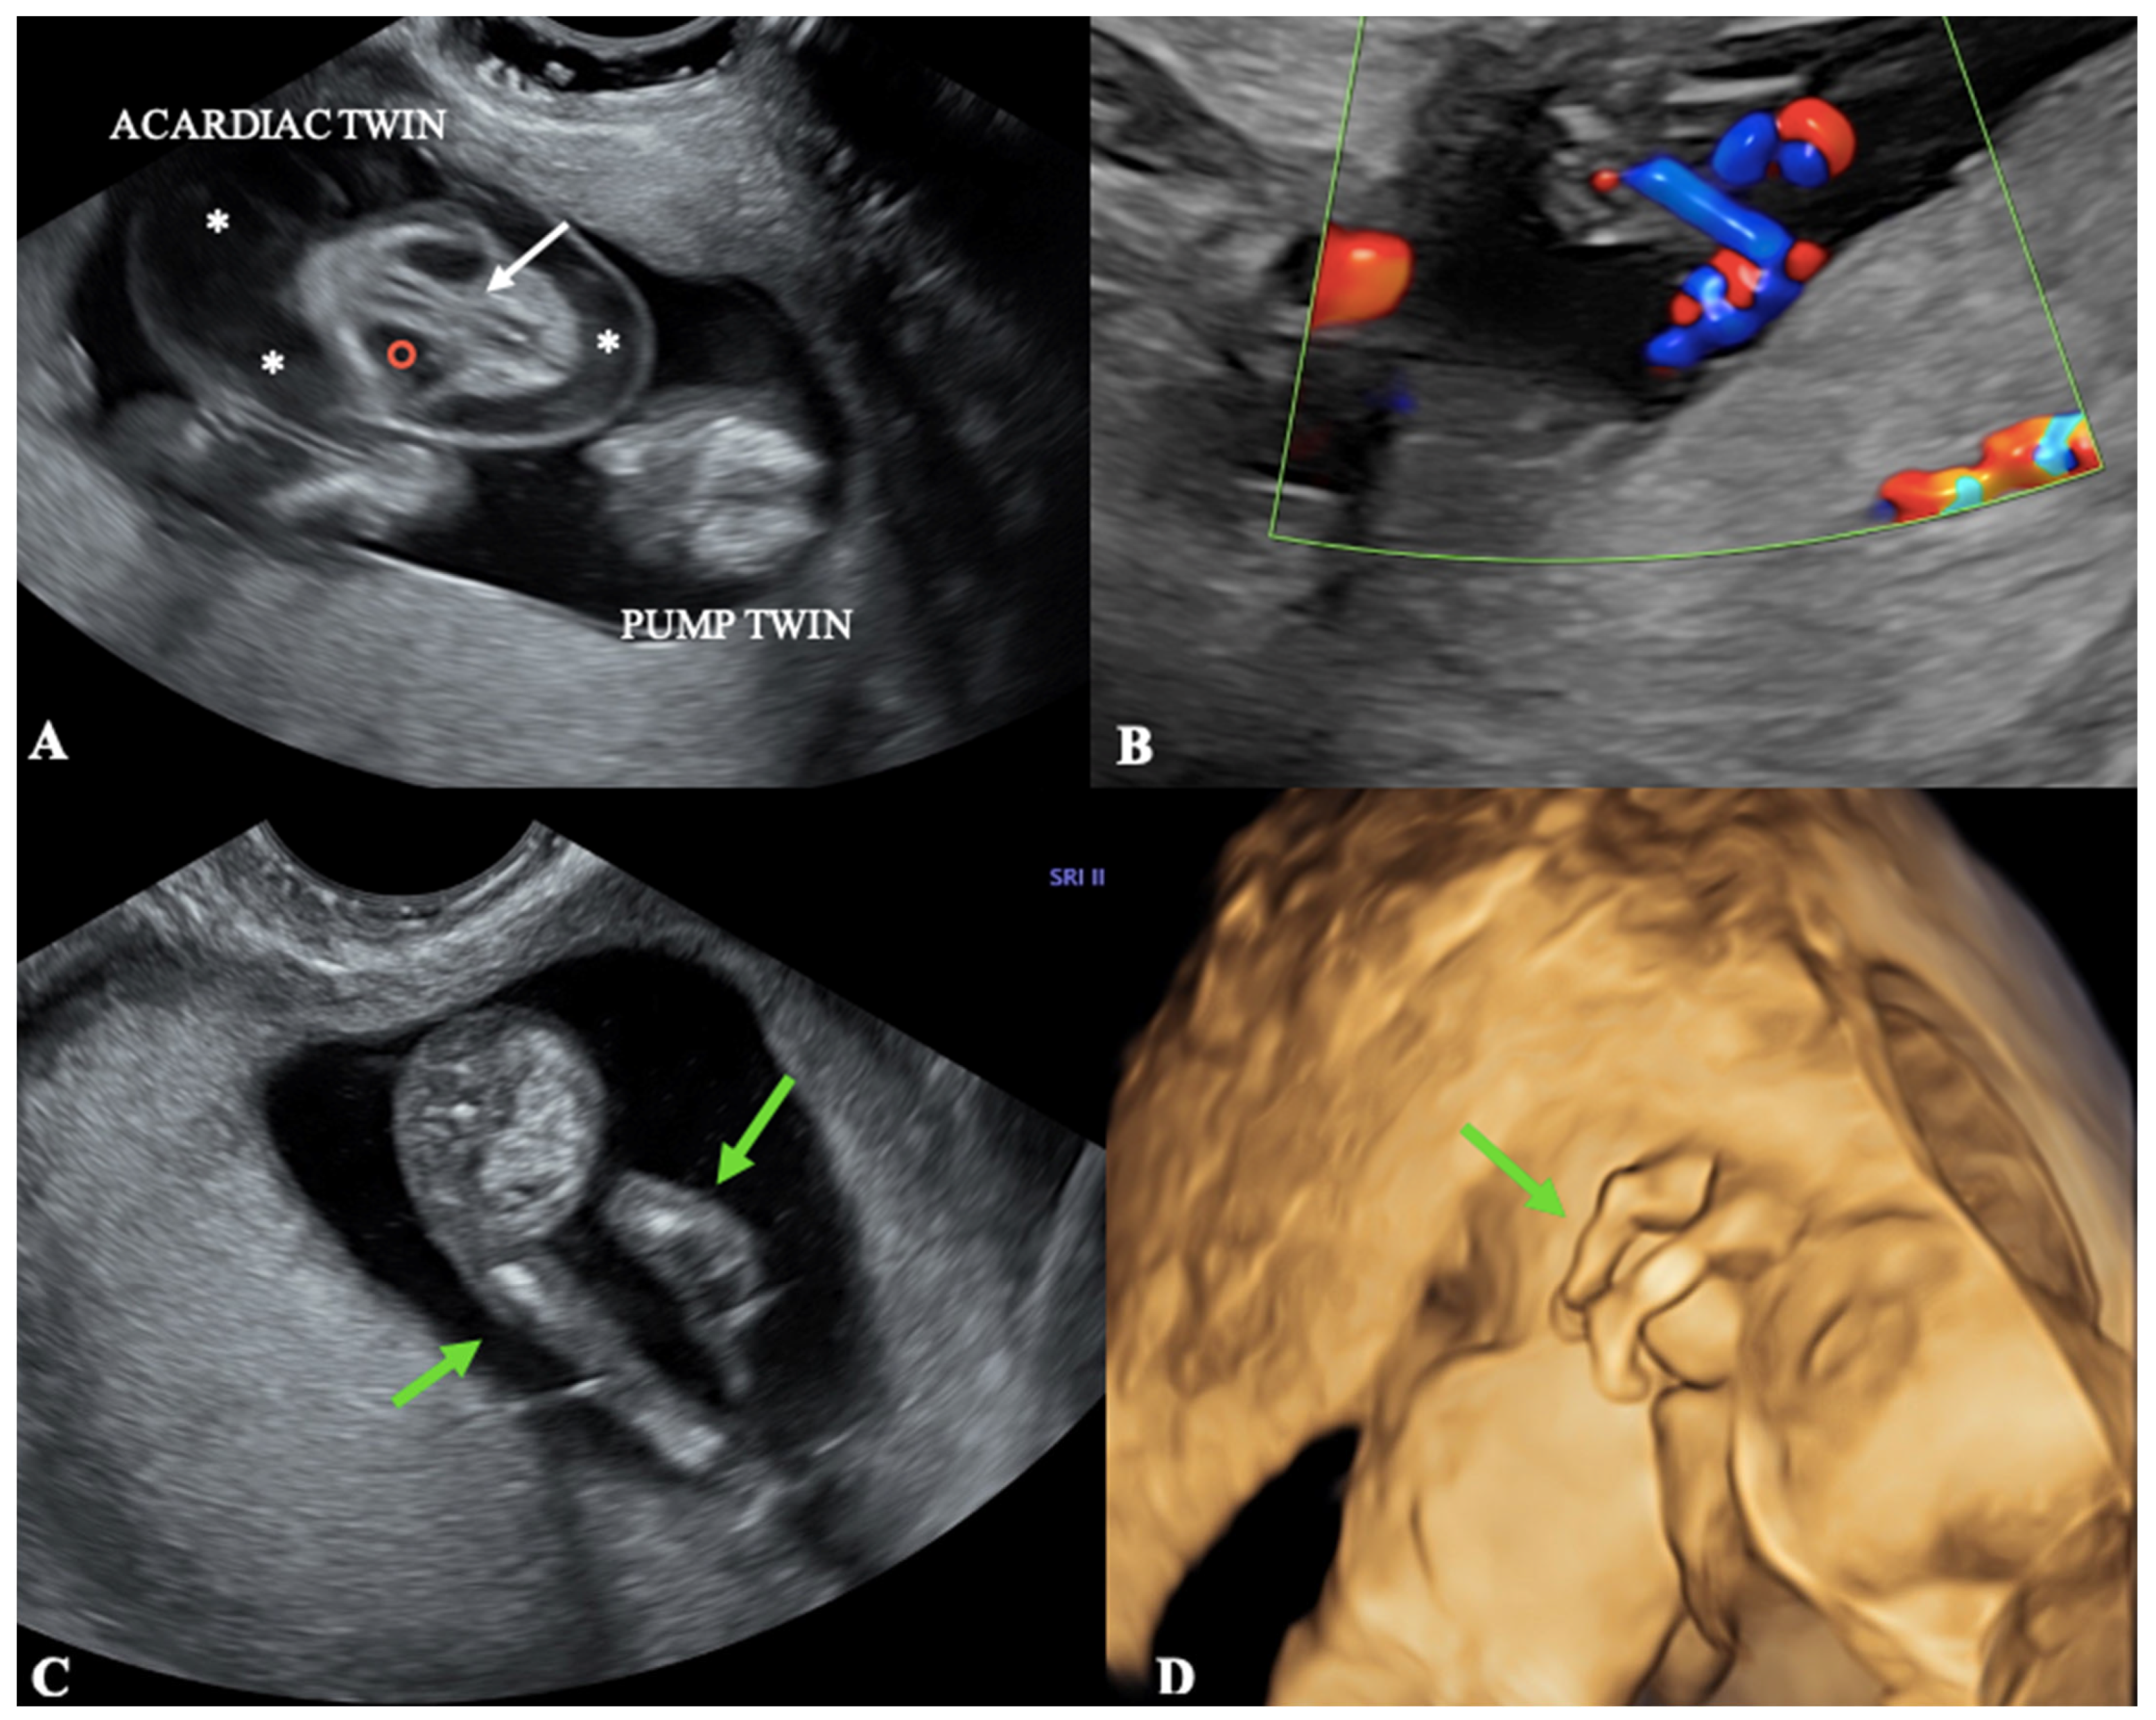

- The most common subtype is the Acardius acephalus, in which the pelvis and lower limbs are well developed, the head and thoracic organs are missing, and poorly developed upper extremities may be present or absent.

- The Acardius anceps is the most developed subtype, since both the upper and lower extremities are present and typically well-formed, and head and face are present too, although poorly formed.

- The Acardius amorphus is the least developed subtype, a shapeless mass without differentiable organs, extremities, or anatomic structures.

- The Acardius acormus is an extremely rare subtype; here, the head is the only recognizable organ.